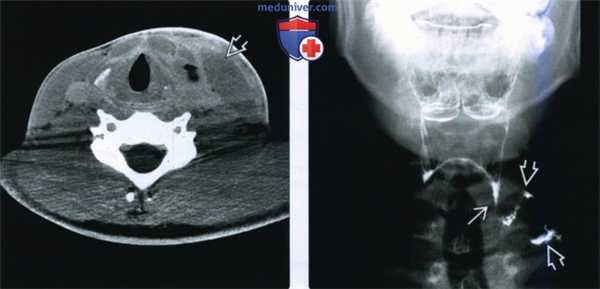

(Слева) На поперечной сонограмме у ребенка в возрасте 16 месяцев визуализируется крупное однокамерное кистозное образование с большим количеством эхогенных включений внутри, подвижных при исследовании в реальном времени. Образование отодвигает яремную вену и сонную артерию в разные стороны, что является признаком, типичным для кисты тимуса. Тем не менее, макрокистозная лимфатическая мальформация может выглядеть также.

(Справа) При аксиальной MPT FSE у этого же пациента визуализируется объемное образование с гиперинтенсивным сигналом, смещающее правую яремную вену и сонную артерию в разные стороны друг от друга, что характерно для кисты тимуса.